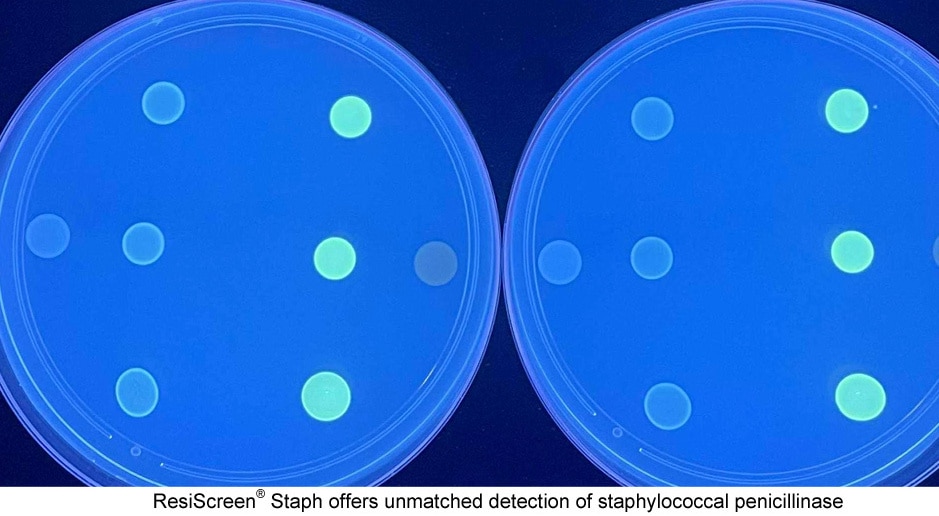

Pour la première fois, bioMérieux publie un livre blanc consacré au sepsis. Il met en...